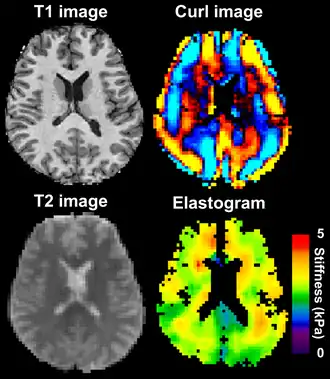

MRE is conducted in three steps: first, a mechanical vibrator is used on the surface of the patient's body to generate shear waves that travel into the patient's deeper tissues; second, an MRI acquisition sequence measures the propagation and velocity of the waves; and finally this information is processed by an inversion algorithm to quantitatively infer and map tissue stiffness in 3-D.[2][3] This stiffness map is called an elastogram, and is the final output of MRE, along with conventional 3-D MRI images as shown on the right.[2]

Magnetic resonance elastography of the brain. A T1 weighted anatomical image is shown in the top-left, and the corresponding T2 weighted image from the MRE data is shown in the bottom-left. The wave image used to make the elastogram is shown in the top-right, and the resulting elastogram is in the bottom-right.

MRE of the brain [27] was first presented in the early 2000s.[28][29] Elastogram measures have been correlated with memory tasks,[30] fitness measures,[31] and progression of various neurodegenerative conditions.[27] For example, regional and global decreases in brain viscoelasticity have been observed in Alzheimer's disease[32][33] and multiple sclerosis.[34][35] It has been found that as the brain ages, it loses its viscoelastic integrity due to degeneration of neurons and oligodendrocytes.[36][37] A recent study looked into both the isotropic and anisotropic stiffness in brain and found a correlation between the two and with age, particularly in gray matter.[38]